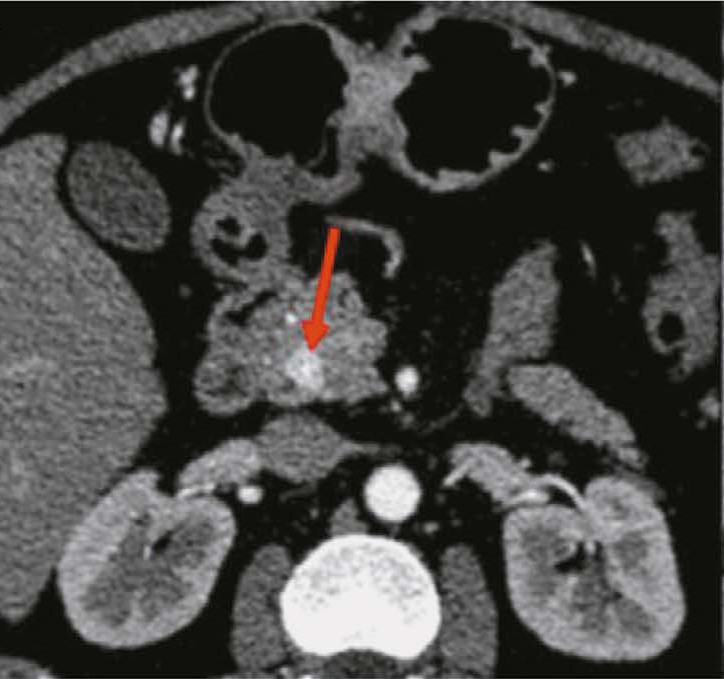

Результаты. На примерах КТ-исследований продемонстрированы типичные и нетипичные визуальные признаки нейроэндокринных опухолей желудка и поджелудочной железы, особенности контрастирования, локализации и структуры новообразований. Выявлено 15 показателей радиомики, которые статистически значимо различаются между нейроэндокринной опухолью желудка и аденокарциномой желудка. В случае поджелудочной железы нейроэндокринные опухоли статистически значимо отличались от аденокарцином по 14 показателям радиомики.